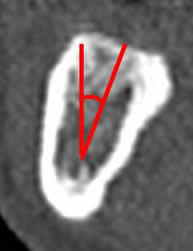

Fig 26. Inclinación de la cresta ósea.

TAC reconstrucción transversal de la mandíbula. Angulo de inclinación, trazado entre la vertical y el eje de la cresta ósea.